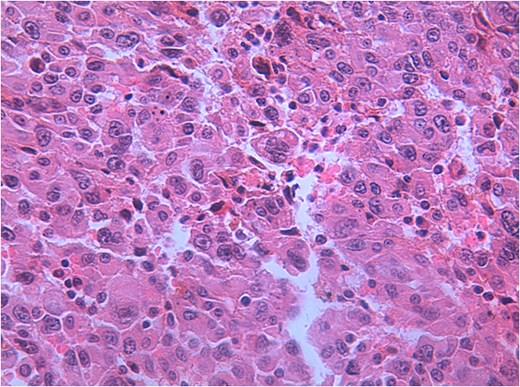

Microscopic evaluation revealed a poorly differentiated neoplasm composed of pleomorphic cells arranged in solid sheets and nests, with high nuclear-cytoplasmic ratio, prominent nucleoli, and brisk mitotic activity. Extensive necrosis was present. Immunohistochemical staining was positive for cytokeratin AE1/AE3 and vimentin, while negative for CK7, CK20, HepPar-1, and chromogranin, supporting the diagnosis of undifferentiated carcinoma. Vascular emboli were identified, and residual tumor cells were present at the resection margin, consistent with an R1 resection. The tumor was staged as pT3NxMx (Figs 5–8).

Hematoxylin and eosin (H&E) staining of the gallbladder tumor showing highly pleomorphic tumor cells with abundant eosinophilic cytoplasm, prominent nucleoli, and frequent mitotic figures, consistent with undifferentiated carcinoma.